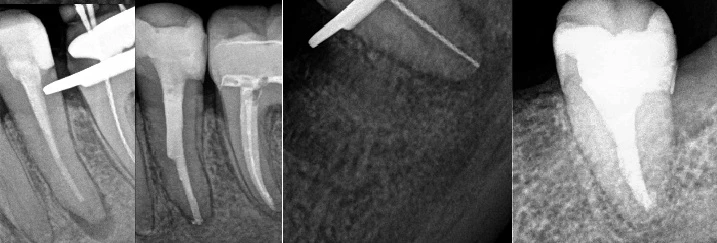

Prawidłowość wykonanego leczenia kanałowego, potwierdza wykonane zdjęcie RVG oraz CBCT.